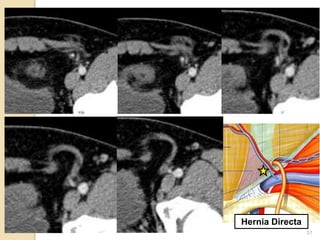

Hernia inguinal directa

Entra al conducto directamente a

traves de la pared posterior

Adquirida

Debido a debilidad muscular

Triangulo de Hesselbach

No atraviesa el conducto inguinal en

toda su longitud

Puede salir por el anillo superficial

Hernia inguinal

Hernia Directa